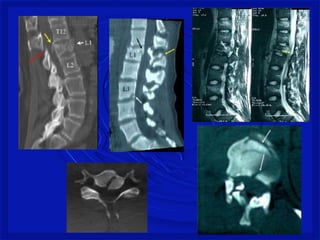

Gravidade do trauma

• DEPENDE SE A MEDULA É ATINGIDA

• Lesão medularcervical é a mais comum– 2/3

• C4 a C7 – mais vulnerável a lesão

• Torácica - proteção de costelas

• Toracolombar– T11, T12 e L1

• Lesão estável ou instável

• Difícil de avaliarno pré hospitalar.

• Considerartoda lesão instável até se prove o

contrario